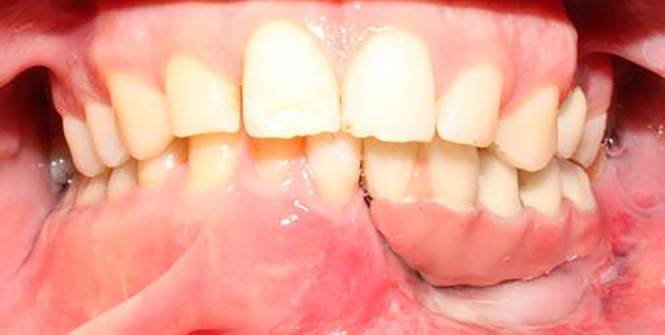

A 30-year-old partially edentulous patient was referred to the Implant Department of Tehran University, School of Dentistry, for prosthetic reconstruction (Figure 1, a and b). The patient had lost 6 teeth due to the trauma of a gunshot. Since the accident had occurred several years prevoiusly and the patient had undergone cosmetic plastic surgery, only a skin scar remained in his lower face. Three implants (Implantium, Dentium, Seoul, South Korea) were placed on the left side of the mandible (Figure 2, a and b). Regarding the increased interocclusal space and improper implant alignment, it was decided to use hybrid screw-retained and cement-retained implant (Toronto) prosthesis.

a) Occlusal view of the mandible after gunshot injury. b) Side view of the left side of the mandible after gunshot injury